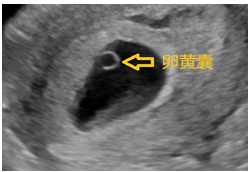

孕6-7周,你的小可爱开始通过超声暗示TA的存在了。此时超声下可以看到暗区内出现了一个小囊泡,它就是我们医学上所说的“卵黄囊”(图3)。卵黄囊其实是胚胎的营养物质,所以卵黄囊的存在多可提示胚胎发育良好。此时的超声告诉我们一个道理:没看到TA,不等于TA不存在。

图3 超声提示:宫内早孕(见卵黄囊)